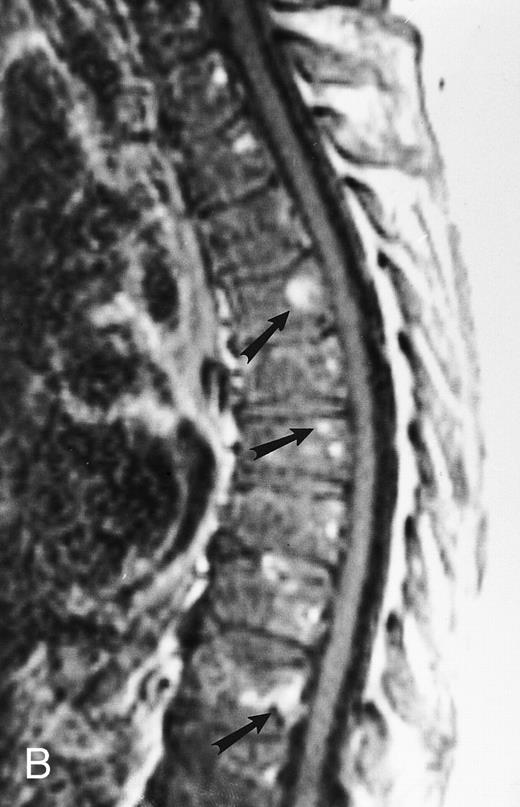

An 8-year-old boy with Burkitt's lymphoma and diffuse marrow involvement. Fat-suppressed, T2-weighted fast spin echo (3000/96, TR/TE) sagittal MR image of the lumbar spine shows heterogeneous signal intensity of the bone marrow and epidural extension of tumor (arrowheads) at the level of L5 and L2, with apparent preservation of the vertebral cortex.